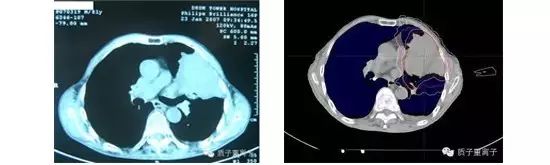

患者男性, 42岁。诊断为左肺肺癌,病理显示腺癌。后患者就诊于当地某医院,共行化疗12周期。复查PET-CT显示:左前胸膜软组织肿块,代谢异常增高,病情明显进展,并考虑肺癌转移灶。患者为求进一步诊治,通过全球肿瘤医生网的全球专家多学科咨询,制定质子治疗方案。治疗后复查CT示肿瘤较前缩小。

左肺肺癌,男性,肺部可见巨大肿块 质子治疗剂量分布图,可见正常肺部组织得到有效保护(下图)

治疗一年后复查,病灶完全消失,局部纤维化(见下图)

七年后再次随访,未见局部复发,无转移。